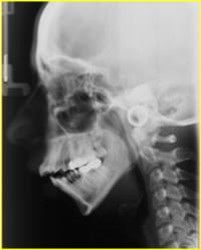

III Classe Iperdivergente morso aperto

Casi Clinici pre - post Chirurgiia Ortognatodontica

casi trattati chirurgicamente dal Prof. Aldo Bruno Giannì